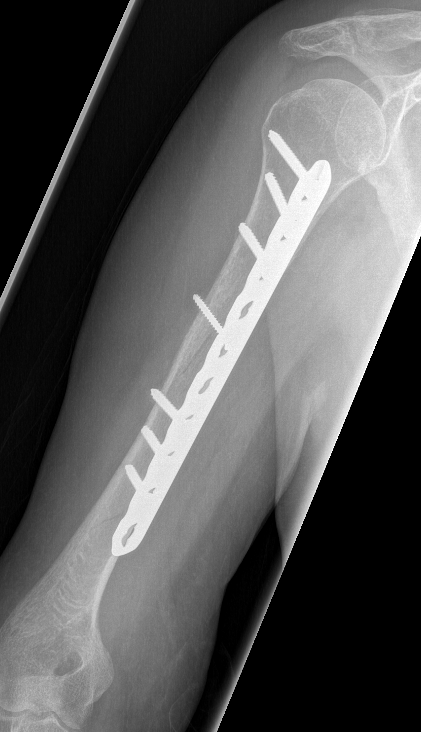

Humeral Fracture SegmentalHumeral Plate LateralHumeral Plate Long AP

Segmental fracture ORIF